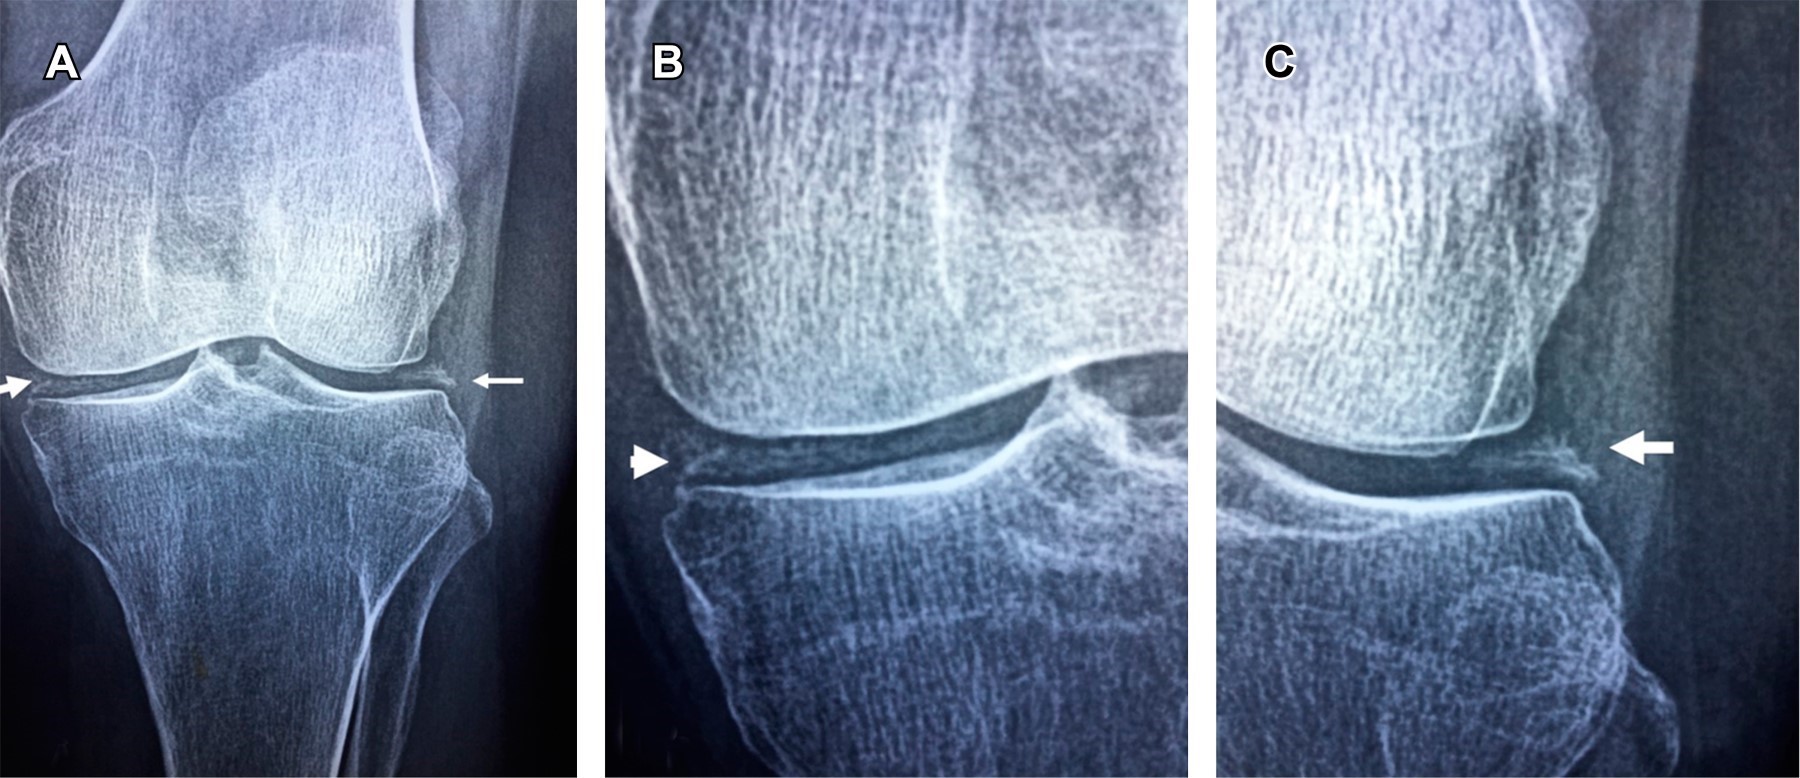

Chondrocalcinosis is not always osteoarthritis in the elderly

Introduction: primary hyperparathyroidism is the third most common metabolic disorder, causing an increase in the parathyroid hormone and serum calcium. It is caused by hyperactivity of the parathyroid glands; in 85% of cases, it is due to a parathyroid adenoma. It is asymptomatic (> 80%), but its manifestations can be musculoskeletal, neurological, psychiatric, renal, cardiovascular, and gastrointestinal. Case report: a 72-year-old female with hypertension, eight months with insomnia, frequent nausea, gastroesophageal reflux, and constipation, presented with left knee pain of two months' evolution without improvement with NSAID. X-ray showed linear meniscal calcification; laboratory studies showed an elevation of serum calcium, ionic calcium, parathyroid hormone, and urinary calcium. The scintigram with Tc99m MIBI showed parathyroid adenoma in the right lower lobe of the thyroid gland. She received surgical treatment; the anatomopathological study confirmed a follicular-type adenoma of the right parathyroid gland. Conclusions: chondrocalcinosis on plain radiography is a frequent finding in elderly people, and most of them will be asymptomatic and will not require treatment. However, whenever it is detected, it is essential to suspect the presence of hyperparathyroidism, so measurement of serum calcium should be part of the daily clinical evaluation of the elderly patient.

Figure 1